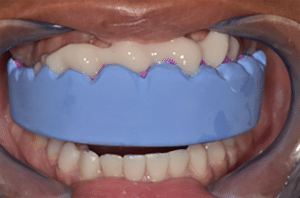

L’occlusion est réglée en statique et dynamique. Il ne reste plus qu’à faire les facettes maxillaires (Fig.15a, b, c).

Fig.15a, b et c : Réalisation des facettes maxillaires. Fig.15a : Mise en place du mock-up.

Fig.15b.

Fig.15c

Très classiquement, selon la technique de Galip Gurel (8), la préparation est réalisée :

– mise en place du mock-up (Fig.15a),

– rainures de réduction contrôlée à travers le mock-up,

– retrait du mock-up,

– finalisation de la préparation en fonction des traces laissées ou pas par les rainures,

– polissage (Fig.15b),

– empreinte numérique (Fig.15c : vue avant et après préparation),

– mock-up pour facettes provisoires.

Dans notre cas clinique, l’usure chimique avait déjà fait tout le travail de préparation. Il a suffi d’arrondir les angles, de réduire un peu la hauteur des bords incisifs et de polir l’ensemble de la préparation. On s’est servi de l’empreinte optique déjà envoyée pour le wax-up antérieur : elle a été dupliquée, coupée de 13 à 23 et les préparations ont été scannées.